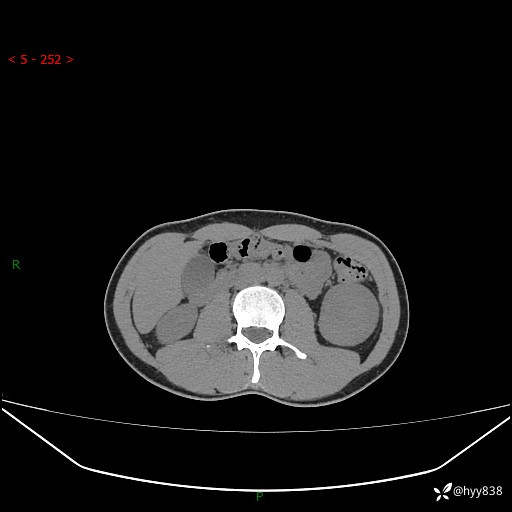

年轻男性,发现左肾占位1天。“非好病例”我不发,误诊率高---(有结果)

现病史:患者昨日中午进食后出现明显腹痛,腹泻,在我院急诊科行补液及对症治疗,双肾输尿管彩超提示左肾占位(5.2*4.3cm),平素无明显腰痛,无再发肉眼血尿等情况,现为求处理左肾占位,遂来我院,门诊以左肾占位收治入院。 患者起病以来,精神、食欲、睡眠尚可,大便可,小便如上,体力体重无明显下降。

双肾CT平扫+增强(三期)